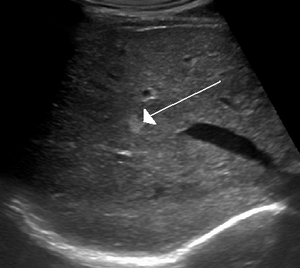

Capillary hemangioma.

The majority of infantile hemangiomas (IH) can be diagnosed by history and physical exam.[6] In rare cases, imaging (ultrasound (US) with Doppler, magnetic resonance imaging (MRI)) and/or cytology or histopathology are needed to confirm the diagnosis.[28][18] IH are usually absent at birth or there may be a small area of pallor, telangiectasias, or duskiness. A fully formed mass at birth usually indicates a diagnosis other than IH. Superficial hemangiomas in the upper dermis have a bright red strawberry color, whereas those in the deep dermis and subcutis, deep hemangiomas, may appear blue and be firm or rubbery on palpation. Mixed hemangiomas can have both features.[6] A minimally proliferative IH is an uncommon type of IH that presents with fine macular telangiectasias with an occasional bright-red, papular, proliferative component. Minimally proliferative IH are more common in the lower body.[29]

If the diagnosis is not clear based on physical exam and growth history (most often in deep hemangiomas with little cutaneous involvement), then either imaging or histopathology can help confirm the diagnosis.[28][4] On Doppler ultrasound an IH in the proliferative phase appears as a high flow soft-tissue mass usually without direct arteriovenous shunting. On MRI, IH show a well-circumscribed lesion with intermediate and increased signal intensity on T1 and T2-weighted sequences, respectively, and strong enhancement after gadolinium injections. There are fast flow vessels.[28] Tissue for diagnosis can be obtained via fine needle aspiration, skin biopsy, or excisional biopsy.[30] Under the microscope, hemangiomas are unencapsulated aggregates of closely packed, thin-walled capillaries, usually with endothelial lining. Blood-filled vessels are separated by scant connective tissue. Their lumens may be thrombosed and organized. Hemosiderin pigment deposition due to vessel rupture may be observed.[31] The GLUT-1 histochemical marker can be helpful in distinguishing IH from other items on the differential diagnosis, such as vascular malformations.[18]